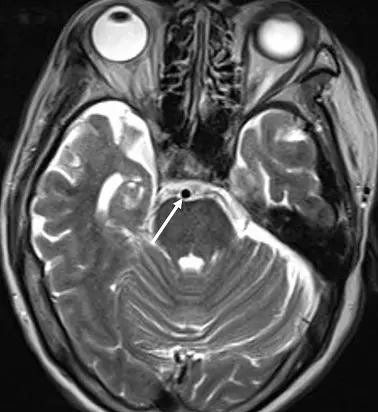

- 影像為一張頭部軸狀切面 (axial plane) 磁振造影影像,切面位置位於橋腦 (pons) 高度。

- 根據影像中腦脊髓液 (CSF)(位於橋腦前池、第四腦室)及眼球玻璃體皆呈現高訊號(亮白色),可明確判定此為 T2 權重影像 (T2-weighted image, T2WI)。

- 白色箭頭所指之處位於橋腦前方的橋腦前池 (prepontine cistern) 內,呈現一個極低訊號(完全黑色)的圓形構造。

- 依據局部解剖學特徵,該圓形構造為基底動脈 (basilar artery) 的橫切面。